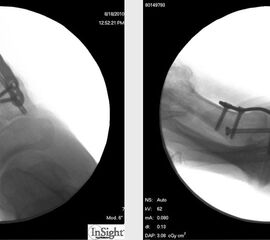

6 Wochen postoperativ Röntgenkontrolle in 4 Ebenen (dorsoplantar, lateral, 45° schräg von medial und lateral). Erscheint die Überbauung noch nicht ausreichend, erfolgt die Mobilisation im „Post-OP-Schuh“ für weitere 2 Wochen mit anschließender erneuter Röntgenkontrolle.

Pseudarthrose: Kommt es innerhalb von 6 Monaten zu keiner knöchernen Durchbauung, ist eine operative Revision indiziert. Ist anhand der normalen Röntgenaufnahmen in 4 Ebenen die Arthrodese nicht sicher zu beurteilen, kann mit Hilfe eines Computertomogramms die Überbauung sicher eingeschätzt werden (Abb. 12). Nach Ausräumung der Pseudarthrose und Spongiosaanlage vom Beckenkamm erfolgt die Reosteosynthese mit einer winkelstabilen Platte. Die Nachbehandlung nach Pseudarthrose umfasst eine 6-wöchige Phase der Entlastung im Castverband. Anschließend Belastungsaufbau nach Röntgenkontrolle. Insgesamt ist die Pseudarthrose eine seltene Komplikation der Arthrodese des TMT 1-Gelenks mit plantarer Osteosynthese.

Zum Lesen der Bildbeschreibung und zur Vollansicht bitte das Bild anklicken.

Abbildung 12